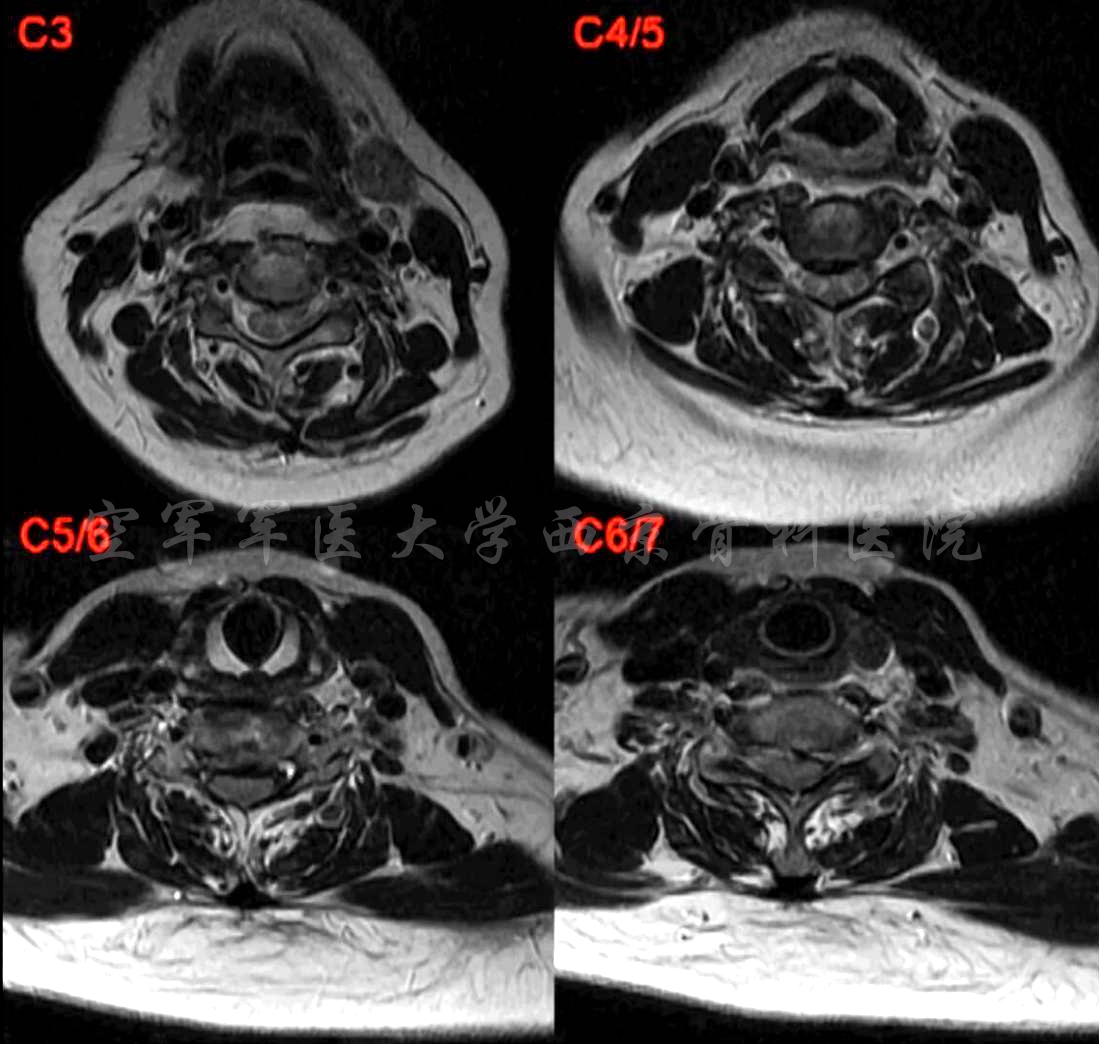

术前MRI